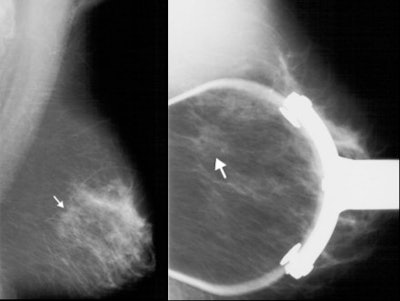

"DBT addresses one of mammography's important weaknesses, which is that of overlapping tissue," explained Joseph Lo, Ph.D. "It can obscure a lesion that is already there, because things are all pancaked together in a conventional mammogram. DBT can also help to better characterize lesions that you do see."

![]() |

| Above, conventional mammogram on which cancer is obscured. Below, DBT slice on which cancer is clearly defined. Images courtesy of Richard Moore and Dr. Daniel Kopans. |